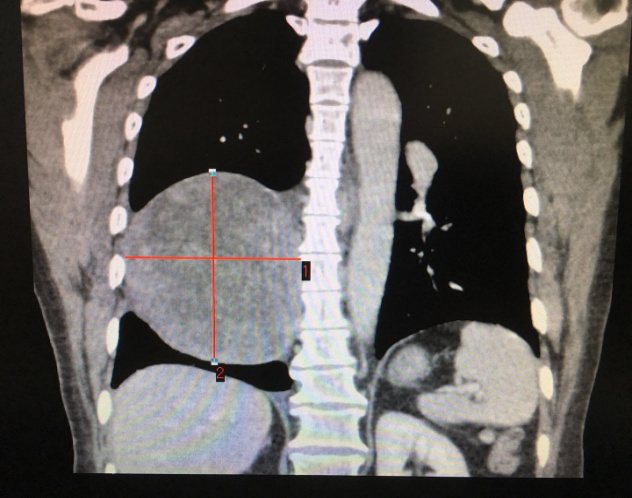

患者CT影像 (標記處為腫瘤)

李旭主任仔細為患者查體,經過嚴密的病情分析后,考慮腫瘤巨大,侵犯心包和下肺組織,決定先行肺穿刺,排除其他惡性腫瘤。最終穿刺病理顯示,陳阿姨患的是神經鞘瘤,這讓李主任松了一口氣:“還有手術的機會!”。